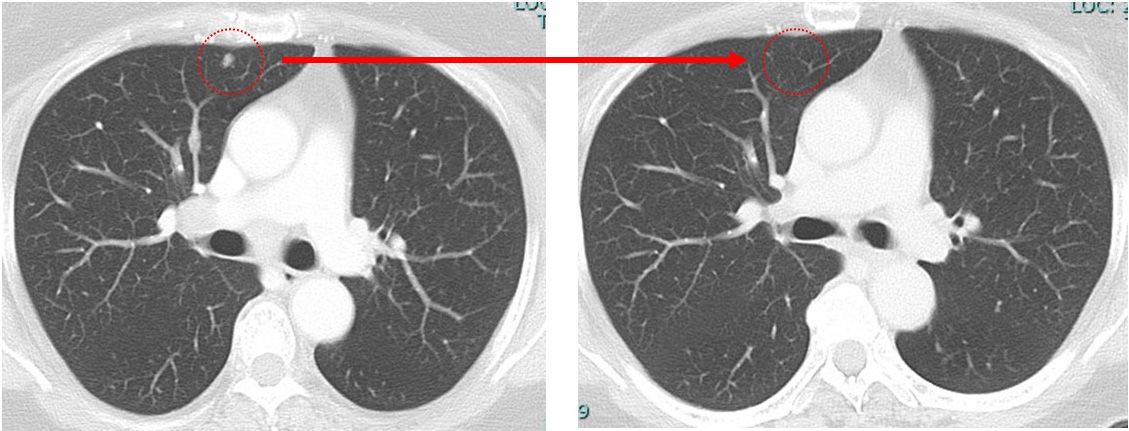

先日MRIをしました所、肝臓は何ともなく、たまたま映った左肺に1箇所腫瘤があったとのことで、造形剤なしのCTを急遽追加でし、同じように左肺に1.3cmの腫瘤が確認されました。

1.肺病変を「転移なのか?の確定診断目的+(局所療法としての)切除目的+(転移ならば)サブタイプを確認する目的」で(胸腔鏡下に)切除⇒その後全身療法

2.まずは全身療法(やはりfirst line はsacituzumab govitecanとなるでしょう)

⇒(肺病変が)消失しないのであれば「ここで」肺の手術

上記1,2どちらにせよ、まずは「画像上完全緩解cCR」 それをどの位維持できるか? この維持が10年を超えた時、それは根治の可能性を秘めてきます。

肺 かなり効いている

肺転移は(分子標的薬だけで)コントロールされている。

①「多発肺転移」は画像上かなり小さくなっているのに「胸の腫瘍は小さくならない」

anthracyclin終了時の時点でのCTでcCR

病変が(少なくとも)画像上消失した状態。